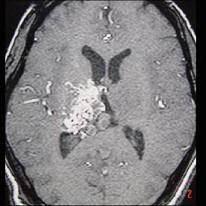

女性,40岁,头晕、头痛两年余,MR检查如图所示,请选择的最可能诊断 ( )A、毛细血管扩张症B、动脉瘤C、动静脉畸形D、毛细血管...

问题 女性,40岁,头晕、头痛两年余,MR检查如图所示,请选择的最可能诊断 ( )

选项 A、毛细血管扩张症 B、动脉瘤 C、动静脉畸形 D、毛细血管瘤 E、海绵状血管瘤

答案 C